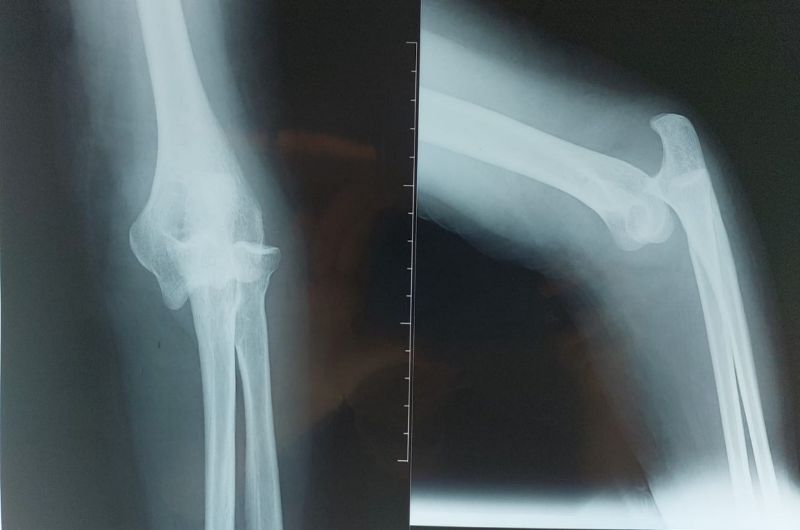

An X-ray of the elbow with AP and lateral views as shown in Figure 5 revealed a posterolateral dislocation of the elbow. The patient was hospitalised and pre-operative bloodwork was done in preparation for a surgical reduction.

Figure 5: Posterolateral dislocation of the elbow joint